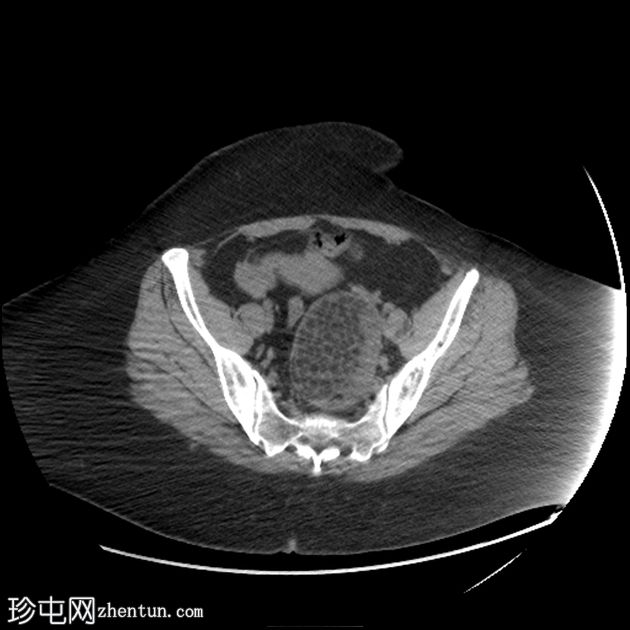

2.jpeg

矢状位

平扫

可见一主要为囊性肿块,大小为10.1 x 7.3 x 8厘米,囊内含有脂肪球。囊壁可见钙化,并对直肠乙状结肠造成压迫。